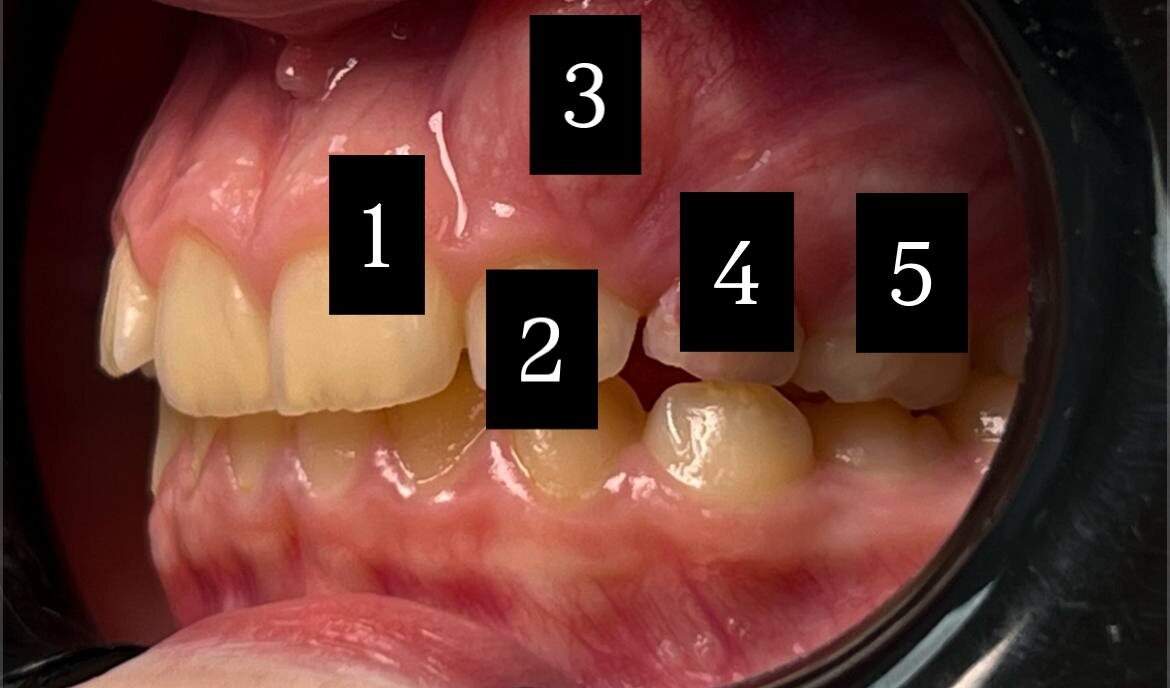

• Ранняя потеря молочного клыка

• Отсутствие попыток заместить пропавший зуб

• Миграция соседнего резца (2) в сторону пустого места.

• Затем туда же смещается центральный резец (1).

• Смещается боковая группа зубов вперёд (4,5).

Вот что происходит дальше:

• соседний резец начинает «ползти» в пустое место,

• за ним смещается центральный резец,

• боковая группа зубов уходит вперёд.

В результате:

• Полное отсутствие места для прорезывающегося постоянного клыка (3).

• Смещение верхней центральной линии.

• Риск травмы коронкой клыка и повреждения корней соседних зубов.